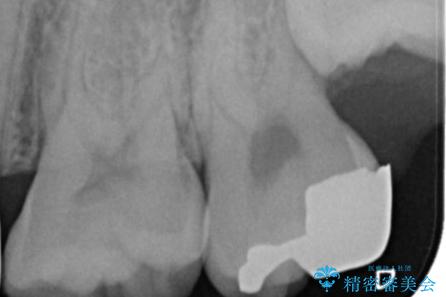

- 銀の詰め物のやり替えを主訴に来院されました。

歯の奥が歯ぐきに埋もれている状態であったため、埋まっている親知らずを抜歯しつつ歯茎の高さを落とし、外れにくいジルコニアクラウンを装着していきます。

歯のみでなく歯茎の調整も行うことで、外れにくい被せ物を装着することが可能になります。